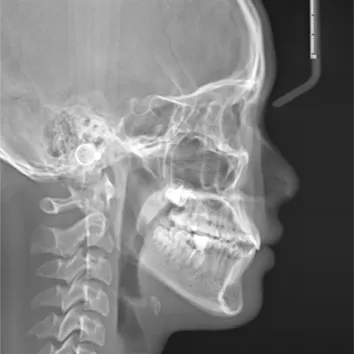

X-rays before treatment

[Panoramic Radiography/Lateral Cephalogram]